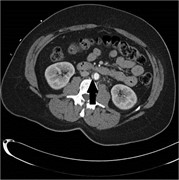

Retroperitoneal calcifying fibrous tumor mimicking an adrenal tumor

Erica C. Prochaska and others

Journal of Surgical Case Reports, Volume 2016, Issue 6, June 2016, rjw049, https://doi.org/10.1093/jscr/rjw049